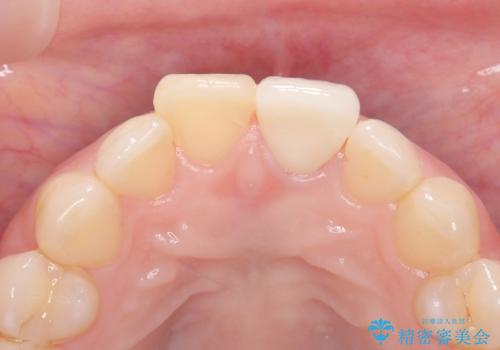

前歯の変色を改善し、本来の自然な美しさへ

治療では、変色した歯を形成した後、精密なシリコン印象材で型取りを行いました。この型取りから、患者様の歯の色や形、透明感を忠実に再現したオーダーメイドのオールセラミッククラウンを作製。金属を一切使わないため、アレルギーの心配がなく、歯ぐきの変色も防ぎます。技工士と連携し、天然歯と見分けがつかないほどの自然な仕上がりを追求。機能性と審美性を兼ね備えた、理想的な前歯を取り戻していただけました。